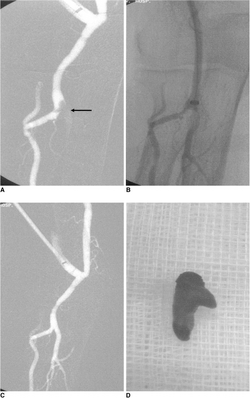

| An embolized fragment of an atrial myxoma (a tumor embolus) at the iliac bifurcation | |